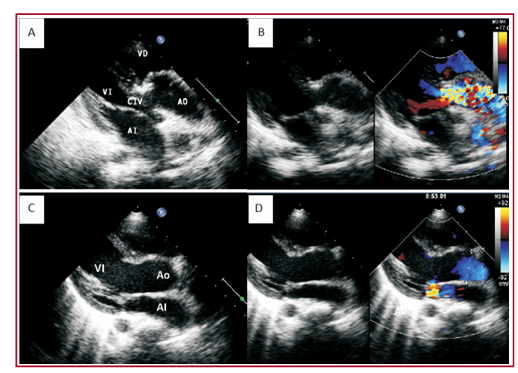

Introducción: La corrección biventricular de la transposición de los grandes vasos con comunicación interventricular y estenosis

pulmonar incluye las cirugías de Rastelli, REV (reparation a l’etage ventriculaire) y Nikaidoh. El tratamiento de elección aún es controversial, dada la gran variabilidad anatómica de esta entidad y los resultados subóptimos de las diferentes técnicas quirúrgicas propuestas.